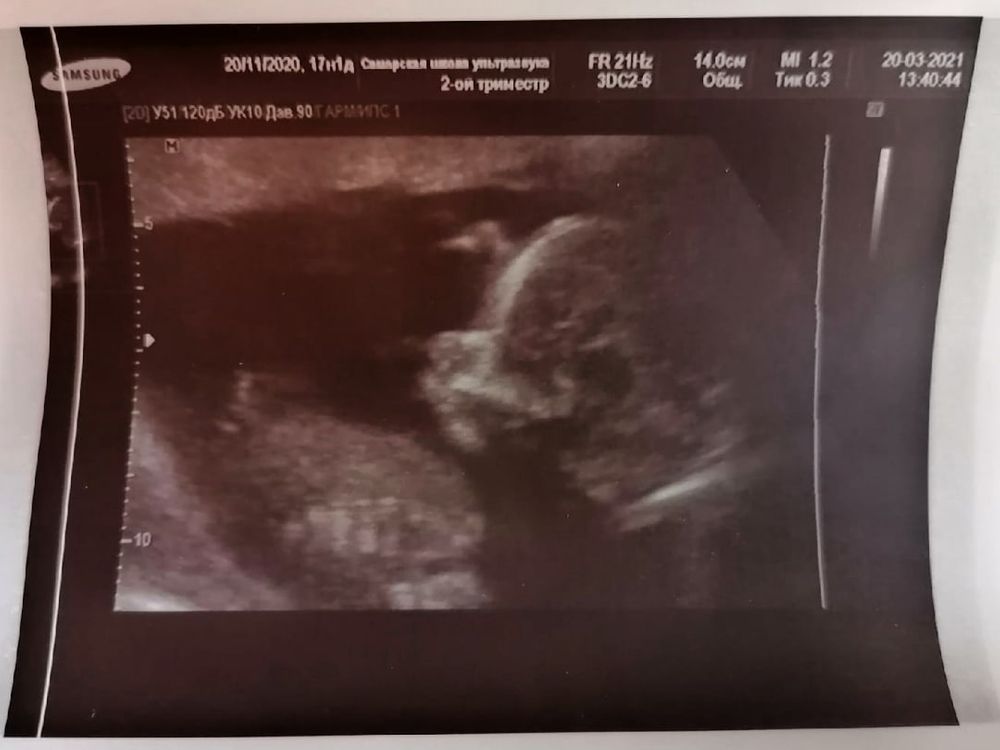

И вот сегодня, в 17+1 с мужем поехали на узи с целью точно узнать, кто же у нас. И сразу же без всяких сомнений узистка сообщила, что это девочка и никакого мальчика она и близко не видит 😄 Малышка позволила рассмотреть себя во всей красе, а потом многозначительно отвернулась мол хватит)))) Моя звезда❤️